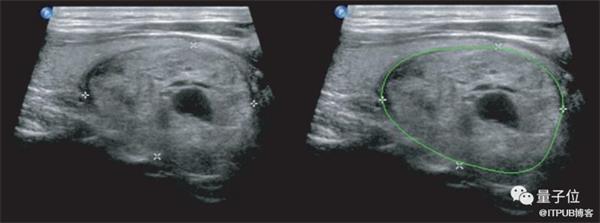

△使用深度学习进行的甲状腺结节检测和定性诊断(右)

这种AI辅助诊断的准确度,当时就已经比中国甲等医院的放射科医生至少高出10%。

当然,这并不是说医学影像AI应用会取代医生,而是让影像科医生在辅助下能有更高的工作效率,也可以让经验丰富的医生专注于更复杂的病例。